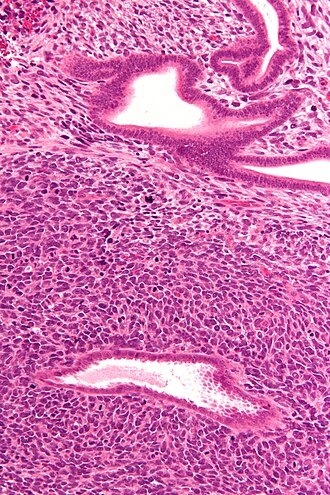

Uterine adenosarcoma. H&E stain.

LM "Malignant stroma" (stromal with nuclear pleomorphism - typically low grade), benign glands with an abnormal shape and "cambium layer" (increased cellularity around the epithelial elements)

Features:[5][1]

• "Malignant stroma" - key feature.

• Stromal nuclear pleomorphism - usually low grade.

• WHO criteria: 2+ mitoses / 10 HPF -- definition suffers from HPFitis.

• Mitotic rate criteria often ignored as mitotically inactive tumours metastasize.[1]

• Benign glands with an abnormal shape.

• "Cambium layer" = increased cellularity around the epithelial elements.[1][6]